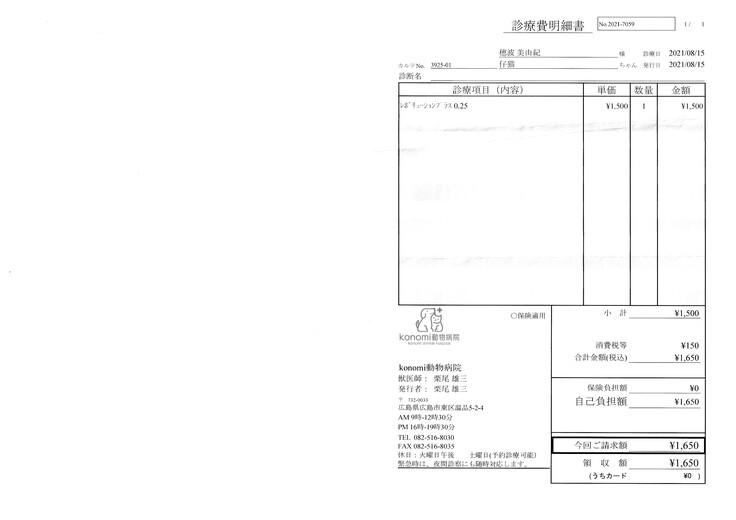

明細書

①入院費用

②退院後の飼育と治療

治療は続いていますが、これまでにかかった費用の一部を皆さまに助けて頂きたく、宜しくお願い致します。

便の中から回虫という寄生虫がでてきました。

入院時に薬を処方してもらっておりましたが、再度処方して頂きました。